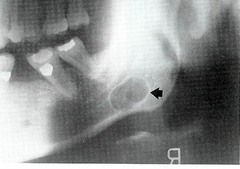

static bone cyst (Stafne)

-asymptomatic, anterior to the angle of the ramus inferior to the mandibular canal -well circumscribed radiolucency in the mandible below mandibular canal -PSEUDOCYST W/ NORMAL SALIVARY GLAND TISSUE